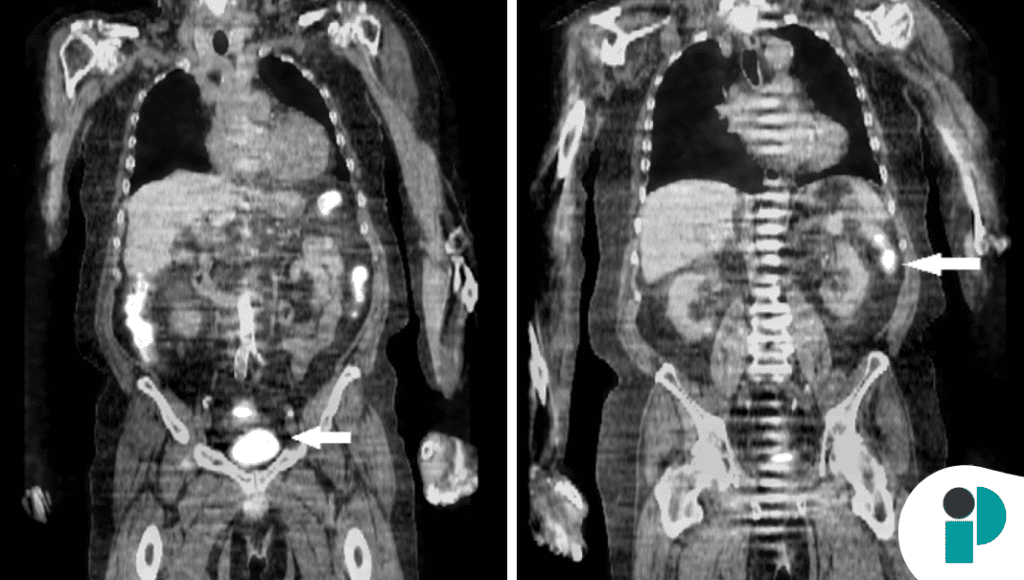

El caso presenta a un paciente con diagnóstico de neoplasia colorrectal en quien, durante la evaluación inicial, se identificó una lesión simultánea en el páncreas distal, lo que generó sospecha de una segunda neoplasia primaria. Sin embargo, este tipo de presentación es extremadamente infrecuente.

Las metástasis pancreáticas suelen originarse principalmente en tumores de riñón, pulmón o colon, pero la aparición sincrónica —es decir, al mismo tiempo que el tumor primario— es excepcional, con muy pocos casos reportados en la literatura.

El reto diagnóstico radica en que estas lesiones pueden simular tumores primarios del páncreas, lo que cambia completamente el enfoque terapéutico y el pronóstico del paciente.

Este caso resalta que, aunque raras, las metástasis pancreáticas deben considerarse en pacientes con cáncer conocido, especialmente cuando se identifican lesiones atípicas en estudios de imagen.